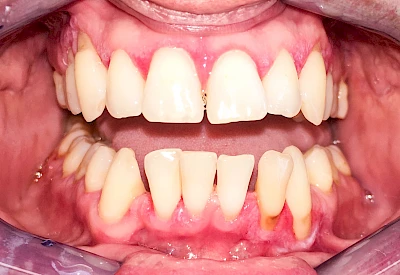

Ist zunächst nur das Zahnfleisch von der Entzündung betroffen, spricht man von Gingivitis. Später, wenn auch der Knochen um die Zähne herum entzündet ist, spricht man von einer Parodontitis. Bei der Parodontitis wird der Knochen nach und nach abgebaut und das Zahnfleisch zieht sich zurück. Die Zahnhälse und Zahnwurzeloberflächen liegen mehr und mehr frei. Die Zähne werden zunehmend lockerer und fallen schließlich aus.